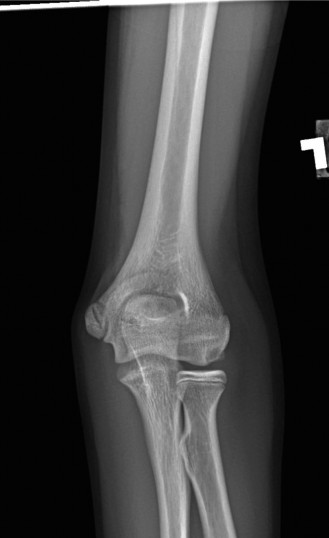

A 9-year-old, baseball pitcher presents to the office with 4 weeks of elbow pain of his throwing arm. He deni…

A 14-year-old baseball pitcher presents to the office with left throwing elbow pain for the past two months w…

A 55-year-old, right-hand-dominant male presents to the office complaining of medial-sided, right elbow pain …

A 45-year-old, right-hand-dominant, male plumber presents with elbow pain of insidious onset. He denies any i…